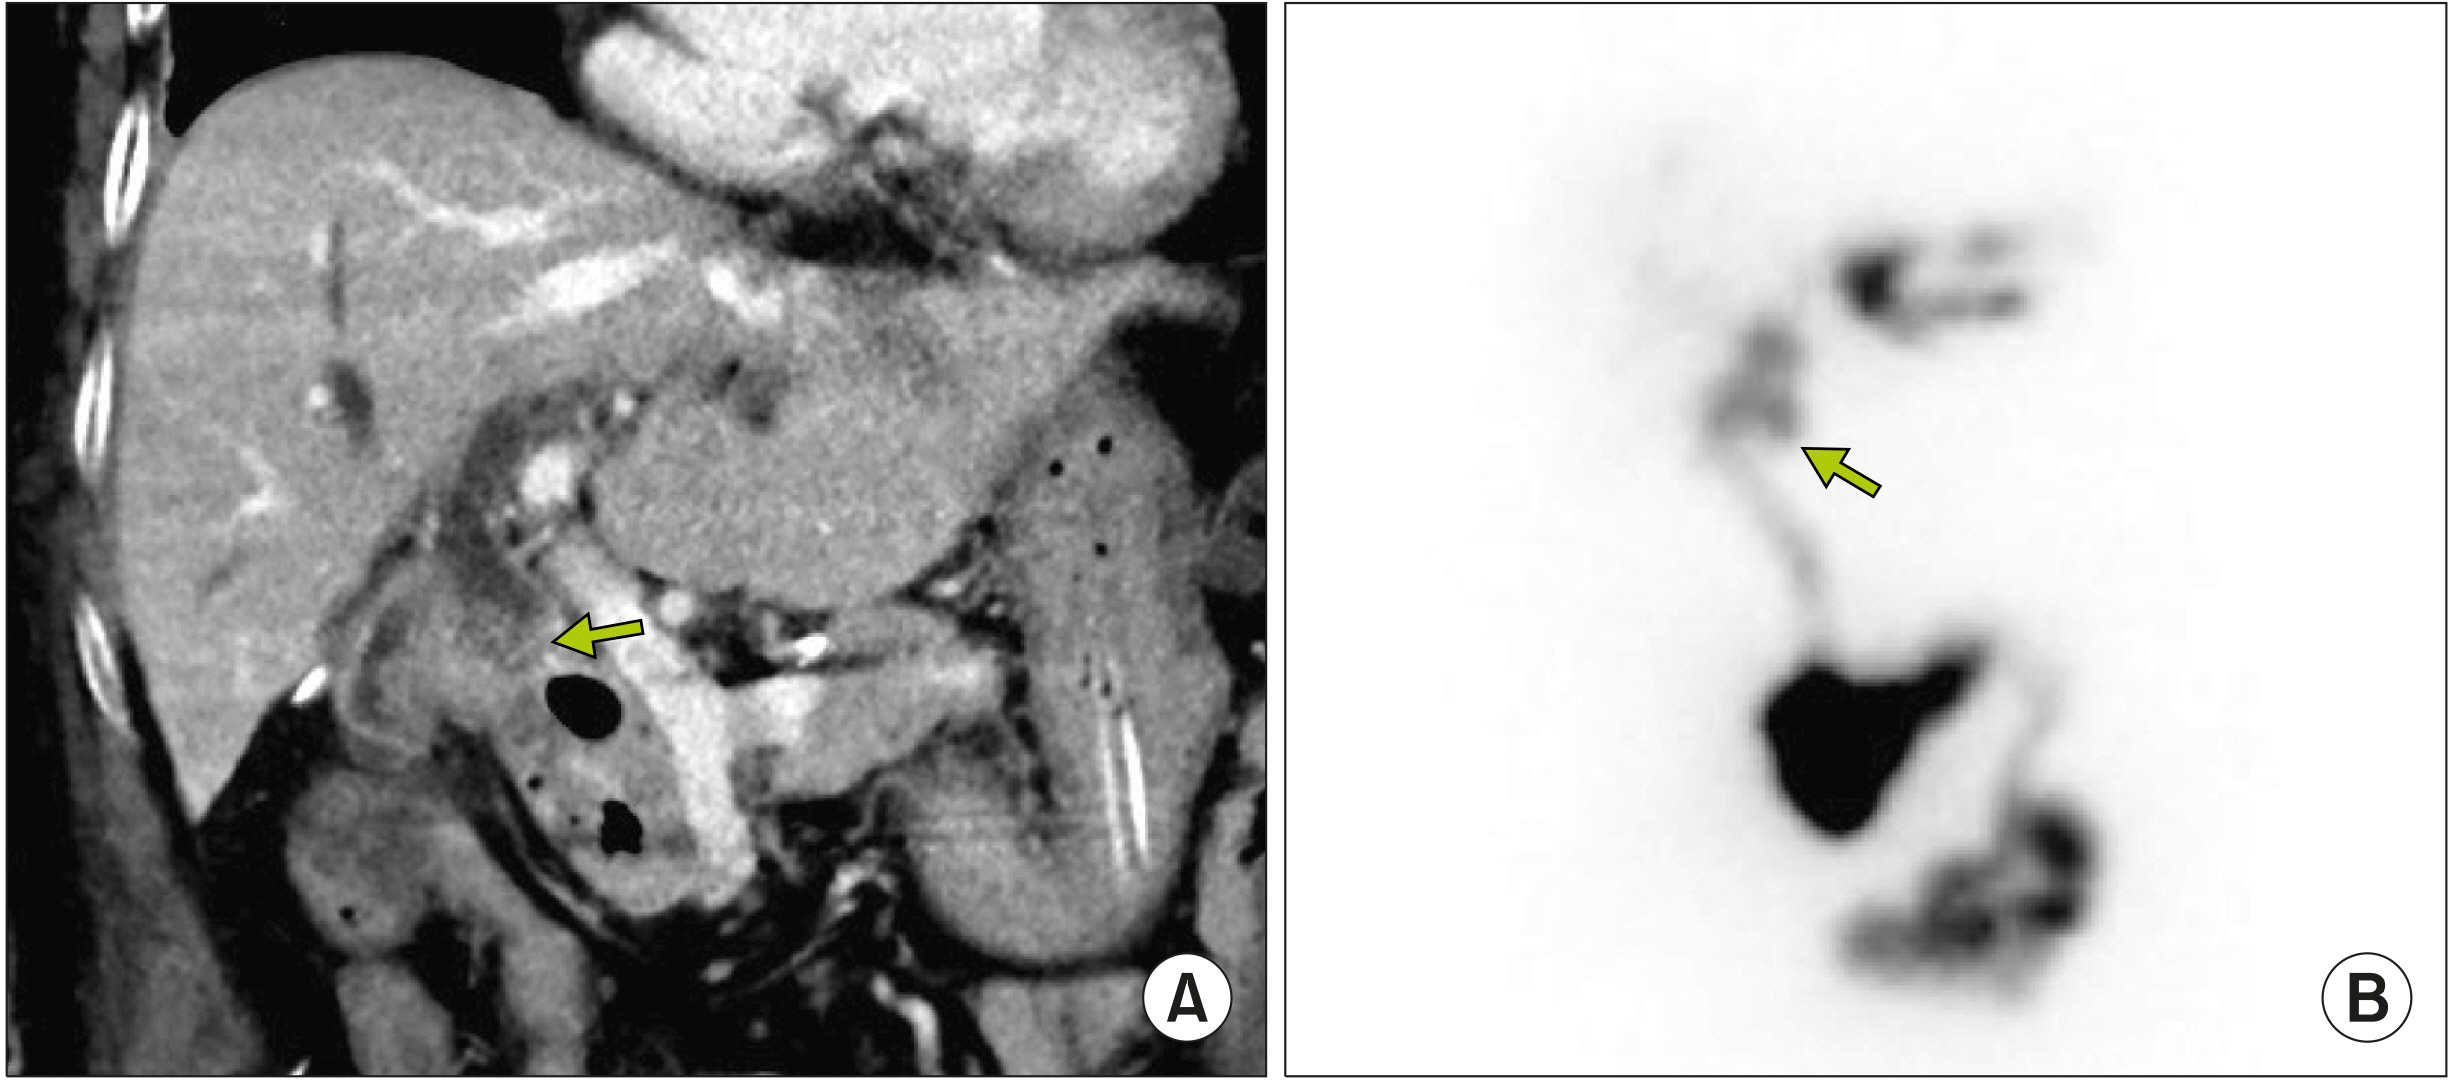

- Despite development in endoscopic treatment and minimally invasive surgery for choledocholithiasis, there remains a small number of patients who require bypass Roux-en-Y choledochojejunostomy (RYCJ) because of the intractable occurrence of common bile duct (CBD) stones. We herein present the detailed procedures of open RYCJ customized for intractable choledocholithiasis. The first method is a side-to-end choledochojejunostomy with intraluminal closure of the distal CBD. This method was applied to a 79-year-old female patient who underwent endoscopic retrograde cholangiopancreatography (ERCP) more than 10 times in the past 14 years (Case No. 1). The distal CBD was explored through choledochotomy and then the distal CBD lumen was occluded with internal running sutures. A large-sized choledochojejunostomy was performed. The patient recovered uneventfully and has been doing well for the past 2 years. The second method is an end-to-end choledochojejunostomy with segmental CBD resection. It was applied to a 75-year-old male patient who underwent ERCP 9 times in the past 10 years (Case No. 2). The CBD was resected segmentally and a large-sized choledochojejunostomy was performed. The patient also recovered uneventfully and has been doing well for the past 2 years. In conclusion, the primary indication of bypass RYCJ is intractable choledocholithiasis which requires numerous sessions of endoscopic stone removal over a long period. Open RYCJ is the preferred procedure to date. If the papilla is patulous, the distal CBD should be occluded or resected to prevent reflux ascending cholangitis. We recommend to resect the intrapancreatic distal CBD if it is markedly dilated like choledochal cyst.